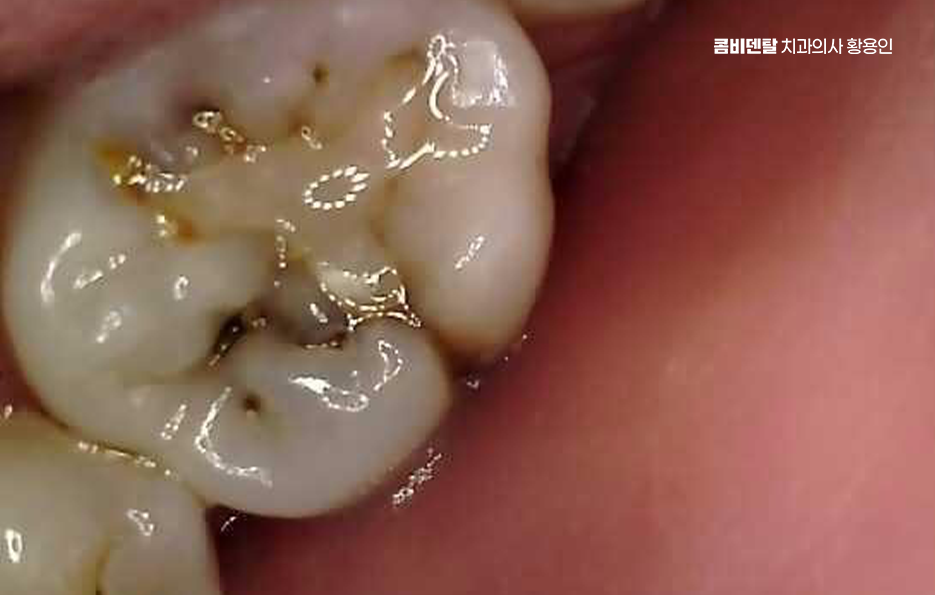

특히 밤에 통증이 심해진다거나, 차가운 물만 닿아도 벌컥 쏘시는 느낌이 있다면 이미 신경에 염증이 깊이 들어간 신경이 감염되어 염증이 진행중일 가능성이 높고 이럴 때는 신경을 제거하고 근관을 소독해서 통증을 줄이는 방식으로 치료를 진행하게 되는 거예요.

치료는 앞니 같이 신경관 수가 적고 간단한 경우에는 12번으로 끝나는 경우도 있지만, 염증이 심하거나 근관 구조가 복잡한 경우엔 34회 정도에 걸쳐 진행되기도 하며 특히 어금니처럼 뿌리가 여러 갈래로 갈라진 치아는 신경이 얇고 구불구불한 경우가 많아서, 그만큼 정밀하게 소독하고 약재를 채워 넣어야 하기 때문에 시간이 더 걸릴 수 있어요.